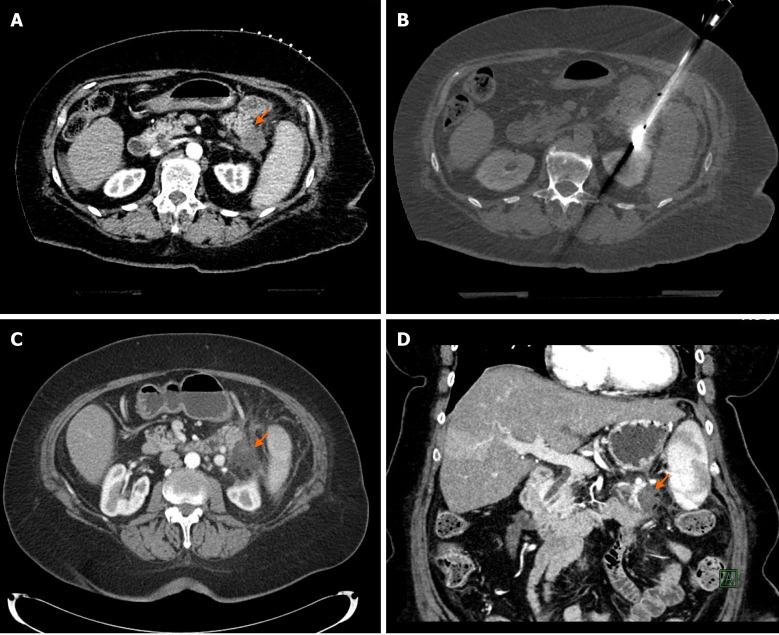

原发性和转移性胰腺癌的微创影像引导治疗。

Minimally invasive image-guided therapy of primary and metastatic pancreatic cancer.

Pancreatic cancer is a challenging malignancy with limited treatment options and poor life expectancy. The only curative option is surgical resection, but only 15%-20% of patients are resectable at presentation because more than 50% of patients has distant metastasis at diagnosis and the rest of them has locally advanced pancreatic cancer (LAPC). The standard of care first line treatment for LAPC patients is chemotherapy with or without radiation therapy. Recent developments in minimally invasive ablative techniques may add to the treatment armamentarium of LAPC. There are increasing number of studies evaluating these novel ablative techniques, including radiofrequency ablation, microwave ablation, cryoablation and irreversible electroporation. Most studies which included pancreatic tumor ablation, demonstrated improved overall survival in LAPC patients. However, the exact protocols are yet to set up to which stage of the treatment algorithm ablative techniques can be added and in what kind of treatment combinations. Patients with metastatic pancreatic cancer has dismal prognosis with 5-year survival is only 3%. The most common metastatic site is the liver as 90% of pancreatic cancer patients develop liver metastasis. Chemotherapy is the primary treatment option for patients with metastatic pancreatic cancer. However, when the tumor is not responding to chemotherapy or severe drug toxicity develops, locoregional liver-directed therapies can provide an opportunity to control intrahepatic disease progression and improve survival in selected patients. During the last decade new therapeutic options arose with the advancement of minimally invasive technologies to treat pancreatic cancer patients. These new therapies have been a topic of increasing interest due to the severe prognostic implications of locally advanced and metastatic pancreatic cancer and the low comorbid risk of these procedures. This review summarizes new ablative options for patients with LAPC and percutaneous liver-directed therapies for patients with liver-dominant metastatic disease.

胰腺癌是一种具有挑战性的恶性肿瘤,治疗选择有限,预期寿命短。唯一的治愈方法是手术切除,但只有 15%-20%的患者在就诊时可切除,因为超过 50%的患者在诊断时已经发生远处转移,其余患者则患有局部晚期胰腺癌(LAPC)。LAPC 患者的一线治疗标准是化疗联合或不联合放疗。微创消融技术的最新进展可能为 LAPC 的治疗手段增添新方法。越来越多的研究评估了这些新的消融技术,包括射频消融、微波消融、冷冻消融和不可逆电穿孔。大多数包含胰腺肿瘤消融的研究表明,LAPC 患者的总生存期得到改善。然而,确切的方案仍有待确定,消融技术可以添加到治疗算法的哪个阶段,以及哪种治疗组合中。转移性胰腺癌患者预后极差,5 年生存率仅为 3%。最常见的转移部位是肝脏,因为 90%的胰腺癌患者会发生肝转移。化疗是转移性胰腺癌患者的主要治疗选择。然而,当肿瘤对化疗无反应或出现严重的药物毒性时,局部肝脏导向治疗可以为控制肝内疾病进展和改善选定患者的生存提供机会。在过去十年中,随着微创技术的进步,出现了治疗胰腺癌患者的新治疗选择。这些新的治疗方法引起了越来越多的关注,因为局部晚期和转移性胰腺癌的预后严重,这些手术的合并症风险低。本文综述了 LAPC 患者的新消融选择以及肝优势转移性疾病患者的经皮肝脏导向治疗。